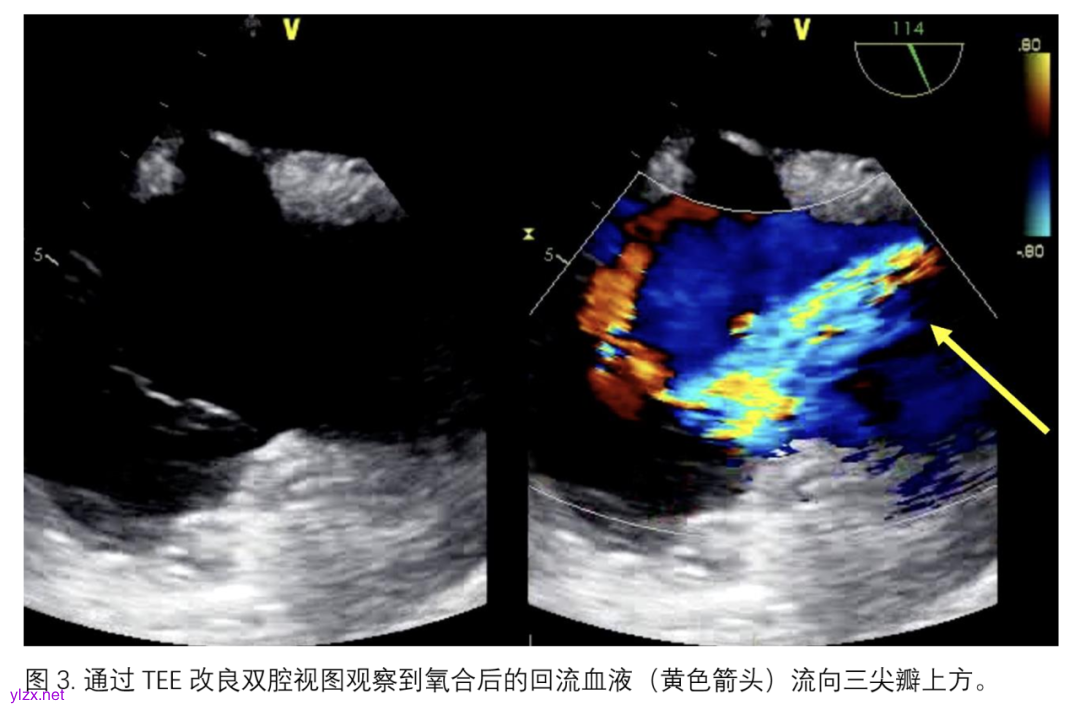

双腔插管的放置可以在透视或经食管超声心动图引导下进行。通过透视确认插管标记指示的流出部位。然而,经食道超声心动图已被很好地用于指导双腔插管的位置,特别是在特殊人群(如COVID-19患者)中,可以避免将患者转运到透视室,并尽量减少对医务人员的暴露。经食道超声心动图的引导是通过中段食管双腔或改良双腔切面实现的。导丝的J形尖端必须被可视化,通过并终止于肝静脉段的下腔静脉,避免进入肝静脉分支或意外进入右心室(图2)。放置位置可以通过在上腔静脉和下腔静脉的插管引流孔处显示湍流,以及通过湍流流出的“射流”指向三尖瓣,且在右心房内几乎没有发散或旋转来进一步确认(图3),以避免诸如心内损伤/右心室穿孔、肝淤血、再循环或结构损伤等并发症[20]。通过对比超声心动图提供高分辨率的影像,可以进一步确认最佳的流动方向,尤其是在有显著肺部病理的患者中,但临床应用比较少。